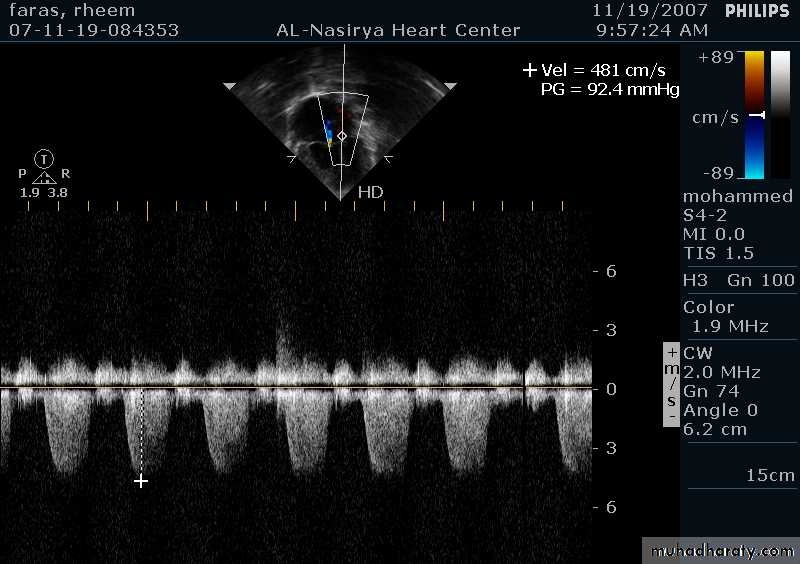

Doppler Echocardiography

Sound waves reflected from moving RBCs undergo frequency shiftThe faster the blood velocity , the greater the frequency shift

The direction of moving blood determines whether the reflected signal is positive or negative

The derived signal can be plotted graphically against timeOr, color can be assigned for the reflected signal and superimposed over the 2D image (color flow mapping)